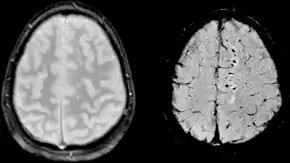

![]() | |

| Two MRI images of a patient with diffuse axonal injury resulting from trauma, at 1.5 tesla field strength. Left: conventional gradient recalled echo (GRE). Right: Susceptibility weighted image (SWI). | |